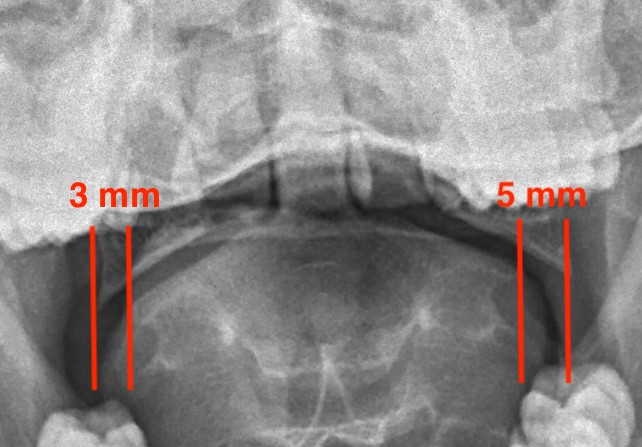

LMD

Lateral mass displacement

LMD 1LMD 2

Increased lateral mass displacement of 8 mm